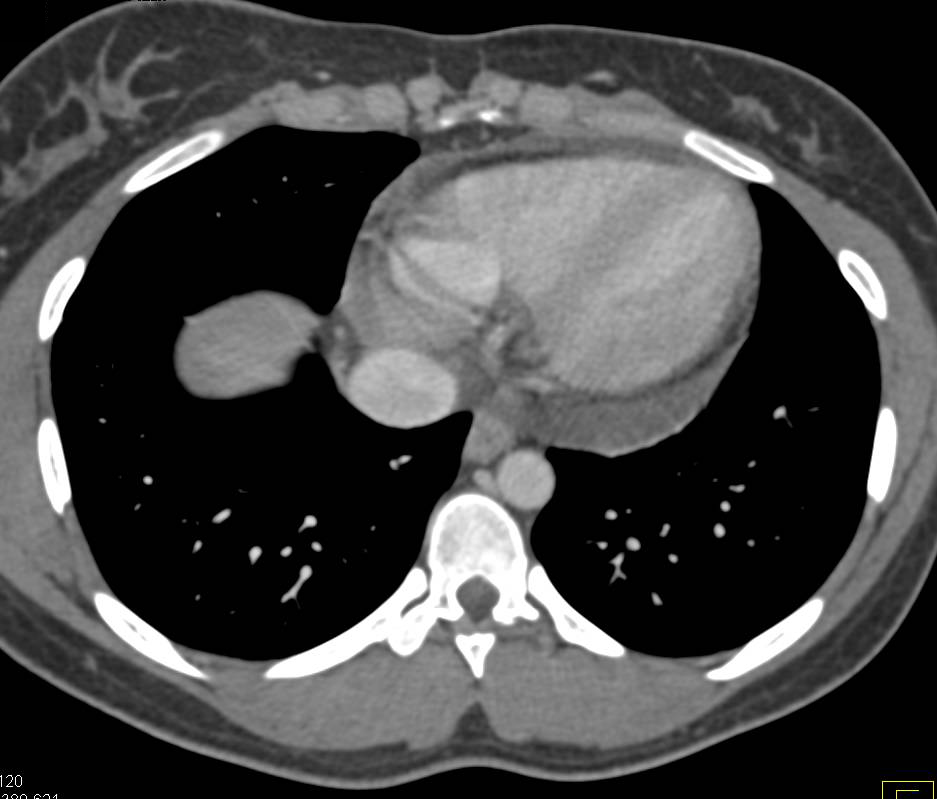

Right Aortic Arch with Aberrant Left Subclavian Artery